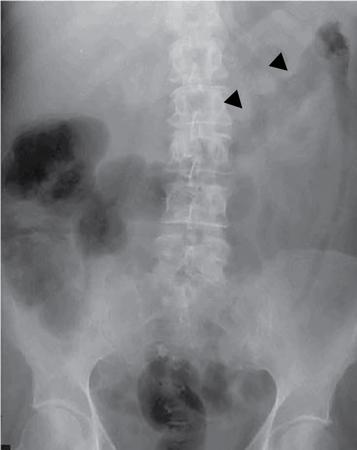

UNDERSTANDING THE ADULT ABDOMINAL RADIOGRAPH: TECHNIQUES AND INTERPRETATION Tanvi Modi Radiography of the abdomen is a common practice for the evaluation of abdominal organs. The anatomy and pathology of digestive, hepatobiliary and genitourinary systems can be assessed using radiographs, either as a stand-alone practice or as a primary imaging modality followed by contrast studies, ultrasound or cross-sectional imaging. In addition, abnormalities of the musculoskeletal or integumentary system can also be deduced on the basis of abdominal radiographs. This chapter intends to give an overview on the techniques and positioning in abdominal radiography as well as interpretation of normal and abnormal features. While superior imaging modalities such as ultrasound, computed tomography (CT), magnetic resonance imaging, capsule endoscopy and the likes have taken over abdominal imaging by and large, radiography still holds a pivotal role in certain situations and conditions, such as: The standard abdominal radiograph is taken in supine position and anteroposterior projection. This is also popularly known as the KUB (kidneys-ureters-bladder) radiograph. Previously, supine as well as erect radiographs were performed in all patients; however, this is not commonly done due to high-radiation dose. For all indications of abdominal radiography, including acute abdomen, supine radiographs are sufficient in terms of radiographic diagnosis, with the exception of perforation for which an erect chest or lateral decubitus radiograph can be performed if there is clinical suspicion. Patient should lie supine on the imaging table with median sagittal plane at right angles to the table and coincident with the midline of the table (Fig. 7.1.1.1). The body is divided into equal right and left halves by the median sagittal which passes through the sagittal suture of the skull. Pelvis should be adjusted so that the anterior superior iliac spines are equidistant from the table top. Gonadal shields, in the case of male patients, should be placed with the upper edge of the shield at the level of pubic symphysis. Although rarely used for female patients, these should be positioned between the anterior superior iliac spines and the pubic symphysis. The centre point of the image receptor should be approximately located at a point 1 cm below the line joining the iliac crests. The X-ray beam should be in a vertical direction, perpendicular to the table top and image receptor at the centre point. Collimation should be such that the soft tissue and subcutaneous region along lateral aspects of the abdominal cavity should be covered within the image. Also, the superior extent involving diaphragm and inferior extent involving the inferior pubic rami is important to look for any lower chest pathologies or any inguinal hernia. 35 × 43 cm (14 × 17 inches) in portrait orientation. On an average, abdominal radiograph exposes a patient to a dose of approximately 1.5 mSv, which is equivalent to 75 chest radiographs or 1/6th dose of a standard CT of the abdomen. The entrance skin dose is approximated to be 4 mGy. At such an effective dose, the additional lifetime risk of fatal cancer is 1 in 30,000. The exposure time is kept short. Patient is asked to exhale completely and hold their breath, with exposure taken at this point of full expiration to ensure imaging of abdominal organs in their natural positions. Modifications of this technique can be made depending on patient habitus and clinical condition. Kilovoltage peak (kVp) should be set to allow adequate visualization of abdominal soft tissue structures as well as semiopaque renal and biliary calculi. Average kVp is set at 70–85 kV. 102 cm (40 inches) Grids are commonly used to reduce scatter radiation. Placement of side marker on the image receptor at the time of radiographic exposure is essential. Bowel pattern depiction should be such that there is minimal lack of sharpness. Standard guidelines for abdominal radiography dictate that the radiograph should extend from the diaphragm up to the level of inferior pubic rami and must include the lateral abdominal wall musculature. The abdomen is divided into four quadrants on the basis of two perpendicular lines (Fig. 7.1.1.7). The vertical line passes through the mid sagittal plane and crosses the umbilicus and symphysis pubis. The horizontal line is a transverse line across the umbilicus at 90 degrees to the vertical line and is situated at the level of L4–L5 intervertebral disc. The quadrants are as follows: Another division system is dividing the abdominopelvic cavity into nine regions using two vertical and two horizontal planes (Fig. 7.1.1.8). The vertical planes, also known as the right and left lateral planes, are parallel to the midsagittal plane between midline and anterosuperior iliac spines on either side. Of the two horizontal planes, the upper transpyloric plane is at the level of lower border of L1 and the lower transtubercular plane is at the level of L5. The nine regions are: On a standard radiograph, the exposure should be such that the stomach, bowel loops, outlines of liver, spleen, kidneys, psoas muscles should be well identified. Also, lumbar transverse processes should be seen. Arch of the pubic symphysis should be visible to evaluate bladder region. A well-centred film without rotation will demonstrate bilaterally symmetrical lower ribs, iliac wings, ischial spines and obturator foramina. Different structures seen on an abdominal radiograph can be classified into five basic densities: Identification of different structures depends on the relative degree of contrast between their densities. The demarcation is clearer in chest and is diminished in abdomen due to relative similar soft tissue density of various structures. On a normal radiograph, relatively large amounts of gas in stomach and colon with minimal small bowel gas can be seen. Further, colonic gas can vary from negligible to extensive, mimicking obstruction pattern; however, usually the gas is enough to delineate colonic haustral pattern. Faecal matter gives a mottled appearance to colonic gas. Short-air fluid levels on an erect radiograph may be seen even in normal cases. The normal appearance of small bowel loops on an abdominal radiograph follows the rule of threes: Stomach is seen in the left upper quadrant and is visualized when distended with air. It is commonly seen extending from T11 to L2 level. Common feature identifying the stomach is the fundal gas which is usually seen as an air fluid level within the gastric lumen. Small bowel loops are distributed to the centre of the abdominal cavity and large bowel loops are peripheral. Duodenum is predominantly situated in right upper quadrant. It extends to left upper quadrant in the region of duodenojejunal flexure. Jejunum occupies the left upper and lower quadrants and is easily identified due to the presence of thick, numerous, closely spaced valvulae conniventes (Fig. 7.1.1.9A). The ileum occupies both lower quadrants and extends into right upper quadrant. Ileum has few and less prominent valvulae as compared to jejunum (Fig. 7.1.1.9B). Ascending and descending colon are retroperitoneal and have relatively fixed positions along lateral aspect of the abdominal cavity on either side. Transverse and sigmoid colon, on the other hand, may have a variable position due to their mobility along mesocolon and redundant pattern. These can be identified with confidence on account of haustrations and faecal matter (Fig. 7.1.1.10). Haustrations are usually well seen in ascending and transverse colon and poorly delineated beyond splenic flexure. Caecum is in the right lower quadrant, though it may be mobile or pulled up. Rectal gas is usually seen in the midline at the level of pelvis and its presence rules out large bowel obstruction. All these positions may vary due to anatomical conditions such as malrotation or pathological conditions, for example volvulus. Liver, spleen and renal outlines cannot be completely traced with precision due to the overlap by bowel loops. On a frontal projection, the liver appears as a triangular structure occupying right and left hypochondrium and epigastric region. Occasionally, the right lobe may be seen extending lower than the right renal shadow. This is a normal variant known as Reidel’s lobe. Gall bladder is situated in the posterior and inferior region of the liver and any pathology of the gall bladder should be looked for in this region. On a lateral radiograph, the gall bladder is anterior to the midcoronal plane. This helps in distinguishing gall bladder calculi from renal calculi, which will be more posteriorly situated. Spleen is seen in left upper quadrant/left hypochondrium, flushed to left lower ribs and left hemidiaphragm. Pancreas is present in the epigastric region (right and left upper quadrants) and is usually not identified in the absence of a pathology. The kidneys are bean-shaped retroperitoneal organs which are seen on either side of the vertebral column and lateral to psoas muscles. Due to the presence of liver on the right side, this kidney is slightly lower in position as compared to its contralateral counterpart. The visualization of kidneys on radiographs is facilitated by the surrounding fatty capsule. Kidneys lie between T11–12 and L2 level, with left kidney 1 cm higher than the right. Psoas muscle shadow can be normally seen along lateral aspect of lumbar spine bilaterally and is mildly concave (Fig. 7.1.1.11). Abdominal wall muscles are not routinely assessed on radiography; however, inclusion of lateral abdominal wall (muscles as well as subcutaneous plane) is a must while performing radiography. The flank stripe or the properitoneal fat stripe is a fat density linear concavity seen along lateral abdominal wall (Fig. 7.1.1.11). It is bound by the paracolic gutters and air-filled ascending and descending colon. All the solid organs in the abdomen are identified due to the fat density outlining them. Distortion of these fat lines helps in identifying organomegaly or focal mass lesions. The dome of urinary bladder is outlined by fat, which aids in differentiating its density from other soft tissue structures of the pelvis. Not all calcifications seen on abdominal radiograph are abnormal. Some may depict age-related changes such as vascular calcifications involving abdominal aorta, pelvic vessels, splenic artery in the region of left upper quadrant. Within the pelvis, phleboliths may be seen and mistaken for urinary calculi. Assessment of lumbosacral spine, iliac bones and femoral heads can be made on the basis of plain radiography. Degenerative changes may be commonly seen. Lower ribs can also be evaluated for pathologies. Dilated small bowel loops with rounded soft tissue density in midline over umbilical region suggests obstruction secondary to umbilical hernia. Pneumoperitoneum must be looked for in all cases of acute abdomen. While erect chest and left lateral decubitus radiographs can detect even 1 mL of free air, there are multiple signs on supine radiograph to suggest this diagnosis, for example Rigler’s sign, falciform ligament sign, football sign (Figs. 7.1.1.24 and 7.1.1.25). Retroperitoneal perforation may demonstrate air outlining psoas muscles and retroperitoneal organs. Small amount of free air may persist in the abdominal cavity up to 3 weeks after surgery, although it usually resolves within a week. Clinical history is important in such cases. Air foci within the bowel wall may represent bowel ischaemia/strangulation. Linear gas patterns in right hypochondrium may be due to two causes, that is pneumobilia and pneumoporta. The former can be seen normally postbiliary surgery, sphincterotomy, ERCP or in the case of abnormal fistulous communication between bowel and biliary tree (Fig. 7.1.1.26A). Pneumoporta (Fig. 7.1.1.26B) is a red flag and warrants further investigation to look for conditions such as mesenteric ischaemia and toxic megacolon. Pneumobilia is more centrally located whereas air shadows in pneumoporta are seen reaching up to periphery of liver. Air foci over renal shadows (Fig. 7.1.1.27), gall bladder or pancreas, in the absence of recent procedural history, suggest fulminant infection and mandate urgent intervention. Central midline calcific foci between T9 and T12 vertebrae can be attributed to calcific pancreatitis (Fig. 7.1.1.28). In the left upper quadrant, areas of calcification seen involving a shrunken spleen may be seen in autosplenectomy. In right upper quadrant, calcified gall stones may be seen. These tend to be small, multiple, uniformly circumscribed and ring-like in appearance with central translucency (Fig. 7.1.1.29A). Mercedes Benz sign, a triradiate pattern of gas lucency, is associated with gallstones. In contrast, renal calculi are more commonly solitary, irregular, of homogenous density, conform to renal calyceal or pelvic outline (Fig. 7.1.1.29B) and are sometimes of staghorn configuration. On lateral view, the gall stones are more anteriorly located as compared to renal calculi, which may be partly superimposed on lumbar vertebrae. Ureteric calculi tend to overlap bony structures such as lumbar transverse processes (Fig. 7.1.1.29B) or sacroiliac joints. Extensive or patchy, curvilinear calcification of gall bladder wall is known as porcelain gall bladder which is often associated with malignant transformation. Calcification involving adrenal glands may be secondary to infection or haematoma, or a congenital condition known as Wolman’s disease where there is bilateral involvement. Discontinuous discrete midline tram track calcification in the abdomen may indicate atherosclerotic changes in abdominal aorta and branch vessels. However, when the calcification is in a globular pattern and seen below the level of L2 vertebra, aortic aneurysm should be suspected (Fig. 7.1.1.30). Appendicoliths, though not commonly seen, may sometimes be detected in right iliac region. Pelvic calcifications: vesical calculi, distal ureteric or vesicoureteric junction calculi, calcified fibroids, ovarian dermoid with tooth-like calcifications (Fig. 7.1.1.31) may be the cause of abdominal pain and should be diligently looked for. Vesical calculi are usually more large and central in location whereas calcification due to fibroids may be more lateral. Schistosomiasis is another cause of bladder wall calcification, as is calcification of bladder tumours. Phleboliths tend to be bilaterally symmetrical, with a lucent centre unlike ureteric calculi. While it is believed that phleboliths are located below the level of ischial spines and ureteric calculi above, this is not always true and should be confirmed with CT. Fluid may collect adjacent to properitoneal fat line, forming a linear soft tissue density separating the fat line from the ascending or descending colon. Hellmer’s sign demonstrates medial displacement of lateral edge of liver (hepatic angle), due to fluid collection or ascites. Gross ascites may appear as generalized abdominal haziness or diffuse increased density of pelvis. Abscesses can involve any solid organ and in such cases may be difficult to demonstrate on plain radiography alone. Enlargement of organ or faint gas densities within can be suggestive of the same. In the case of peritoneal abscess, mottled density due to air, fluid and necrotic contents point towards this diagnosis, especially in right iliac fossa in association with appendicitis. Retroperitoneal abscess, similar to any retroperitoneal mass, may cause displacement of retroperitoneal structures (Fig. 7.1.1.32). Subdiaphragmatic abscesses may show concomitant ipsilateral pleural effusion (Fig. 7.1.1.33). These should be differentiated from Chilaiditi syndrome. Fluid and soft tissue lesions present with the same density on radiographs. While it is difficult to characterize the lesion and organ of origin, clues for the same can be provided by organomegaly (Fig. 7.1.1.34), distortion of fat surrounding solid organs, displacement of bowel loops or solid organs. For example, a retroperitoneal lesion may cause anterior or inferior displacement of kidney, a pelvic mass may cause upward displacement of small bowel loops. Different densities such as fat or calcification may help in identifying organ of origin (e.g. fat and tooth densities seen in ovarian dermoid). Convexity of margins of psoas muscle on an abdominal radiograph can be due to haematoma, abscess or intramuscular tumour. Radiographs are performed for the initial diagnosis of foreign body in the abdomen including type, number of foreign bodies, location, size and shape (Fig. 7.1.1.35). Radiolucent foreign bodies such as wood, plastic, chicken bones will not be easily identified on radiography. Low kVp (65–70 kVp) can increase contrast and help identify these objects. In addition to an abdominal radiograph, chest radiography is also performed to exclude aspiration or oesophageal location of foreign body. Ingested or introduced foreign bodies may cause complications such as obstruction, perforation, fistula formation and sepsis. Hence, once their presence is confirmed, follow up radiography must be performed until they are eliminated. One must look for fractures/dislocation injuries involving the vertebrae or pelvic bones, especially after history of trauma. Lucent expansile lesions or sclerotic bony deposits which represent neoplasms, absent pedicle sign in cases of metastasis, metabolic bony changes such as rugger jersey appearance, Paget’s disease, arthropathies such as ankylosing spondylitis with bamboo spine appearance and sacroiliitis (Fig. 7.1.1.36) are some of the conditions which may be diagnosed based on an abdominal radiograph. Overlap of bowel loops over iliac blades may lead to a misdiagnosis of lucent lesions and should be evaluated with caution. Basal pneumonia may be the cause of acute abdominal pain and should be looked for in abdominal radiography. Similarly, pleural effusion, pericardial effusion, calcified pleural plaques, achalasia, interstitial fibrosis are few other findings that can be seen in lower chest on an abdominal radiograph. Basilar atelectasis can give a deceptive appearance of pneumoperitoneum (Fig. 7.1.1.37). Surgical clips, commonly in right hypochondrium after cholecystectomy, drainage tubes, ventriculoperitoneal shunts, femoral line catheters, IVC filters, stents (vascular, renal, biliary) (Fig. 7.1.1.38), stoma bags, contraceptive devices are some structures that may be seen in an abdominal radiograph. Correct knowledge of patient history and normal locations of these structures prevents misdiagnosis. Certain artefacts may be projected upon the radiograph due to surface structures such as trouser buttons, body piercing, sequins over clothing and should not be considered as a pathology. Multiple skin surface nodules in cases of neurofibromatosis, soft tissue focal swellings, such as abscesses, lipomas, haematomas, desmoid tumours and malignant lesions may be incidentally seen on radiography. These can be further evaluated using ultrasound or CT. Subcutaneous emphysema is another finding that may be seen in lower abdominal wall secondary to retroperitoneal perforation or diffusely along abdominal wall in the case of bowel perforation (Fig. 7.1.1.39). Foreign bodies such as bullets and pins may be seen lodged in abdominal wall. A systematic approach to abdominal radiographs is important for accurate diagnosis as follows: Despite the development of newer techniques for imaging of the abdomen, plain radiography still holds an important place in the initial assessment of acute abdomen. Positive and negative findings on an abdominal radiograph can direct further investigation. Ideal positioning, recognition of normal appearances and keen scrutiny for pathologies is a sine qua non for radiologists reading a plain film of the abdomen. OESOPHAGOGRAM Padma V. Badhe, Vikram Reddy, Sultan Moinuddin Shaukatali, Zillani Alam, Ravi Varma, Abhishek Bairy, Dasari Ravikiran, Revati Tekwani, Soniya Patankar, Megha Nair, Gautham Shankar Oesophagogram is the process of obtaining radiological images and simultaneous motion recording to evaluate function and disorders of pharynx, oesophagus and proximal stomach. Oesophagogram is usually done primarily to evaluate dysphagia. Some of the common indications are oesophageal motility disorders, strictures, gastro-oesophageal reflux disease (GERD) and suspected masses. It can also be used to detect uncommon anomalies like vascular rings/slings and aberrant anatomy. It also helps to evaluate further in cases where there is inability to pass upper GI scope. Double-contrast oesophagogram is mainly indicated in early mucosal disease like erosion, polyp, infection and tumours. If a motility disorder is suspected, dynamic technique (e.g. videofluoroscopy) is used for dysphagia or aspirations in cases of stroke, neuromuscular disorders, post head and neck surgery or radiation. Barium oesophagogram is contraindicated in suspected cases of perforation and tracheoesophageal fistula, aspiration, rarely if there is hypersensitivity to barium suspensions. It is also contraindicated in suspected oesophageal perforation where a water-soluble contrast agent is more suitable. However, ionic water-soluble contrast agent is better avoided in cases of aspiration or fistula with airway. The contrast examination of the pharynx is dangerous in cases of acute epiglottitis and must be ruled out on plain radiograph. An 80% w/v barium suspension is used in full column views. However, 200%–250% w/v barium suspensions is usually required for mucosal relief films. The barium sulphate mixture is fed to the patient either by spoon, by glass, or through a drinking straw, depending on its consistency. In videofluoroscopy, the pharyngeal phase of swallowing is usually safer with barium pudding than with thick barium and safer with thick barium than with thin barium. However, if the major abnormality is poor pharyngeal contraction leading to stasis in the piriform sinus (and epiglottic tilt is normal), a thin liquid is safer. Epiglottic motility is better assessed with thin barium because thick barium often obscures the epiglottic tip. Fluoroscopic equipment capable of cine fluoroscopy and capability for rapid sequence spot images (high frame rate) is needed for this examination, Barium suspension, straw, glass, Lead apron and radiation protective equipment. The patients are instructed to fast after midnight before the day of the examination. The pharynx should be made as dry as possible during the examination as high-density barium adheres to dry pharyngeal mucosa. Activities like smoking, chewing gum and lozenges must be abstained before the procedure as they impair barium coating by increasing the salivary secretion. Regular oral medications must be taken with sips of water; however, insulin must be skipped on the morning of examination. The major principles of a good oesophagogram includes mucosal coating, distension and projection. A routine oesophagogram consists of screening of the oral, pharyngeal and oesophageal phases of swallowing, single and double-contrast examination of pharynx, single contrast, double-contrast and mucosal relief views of the oesophagus. In cases of dysphagia, the examination is tailored depending on whether the symptoms are either pharyngeal or oesophageal and initial fluoroscopic findings. If patients’ symptoms are suggestive of oral or pharyngeal disorder then pharynx is evaluated first. Similarly, if patient is suspected to have thoracic oesophageal disease then, double-contrast examination of the oesophagus is performed before the pharyngeal evaluation. During an oesophagogram the positioning of the patient varies according to the type of examination (Table 7.1.2.1).